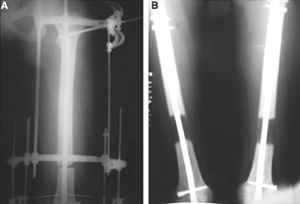

Как вы думаете если сделать следующее.

После заживления раны на левом бедре. Выполнить открытую реподицию и синтез пластиной для дистального бедра. Пластину в проксимальном направлении зафиксировать монокортикально.

А затем выпонить остеотомию бедра в верхней трети.

И тракцию бедра на стержне. Типа (СМ картинки).

После выращивания регенерата стержень блокировать.